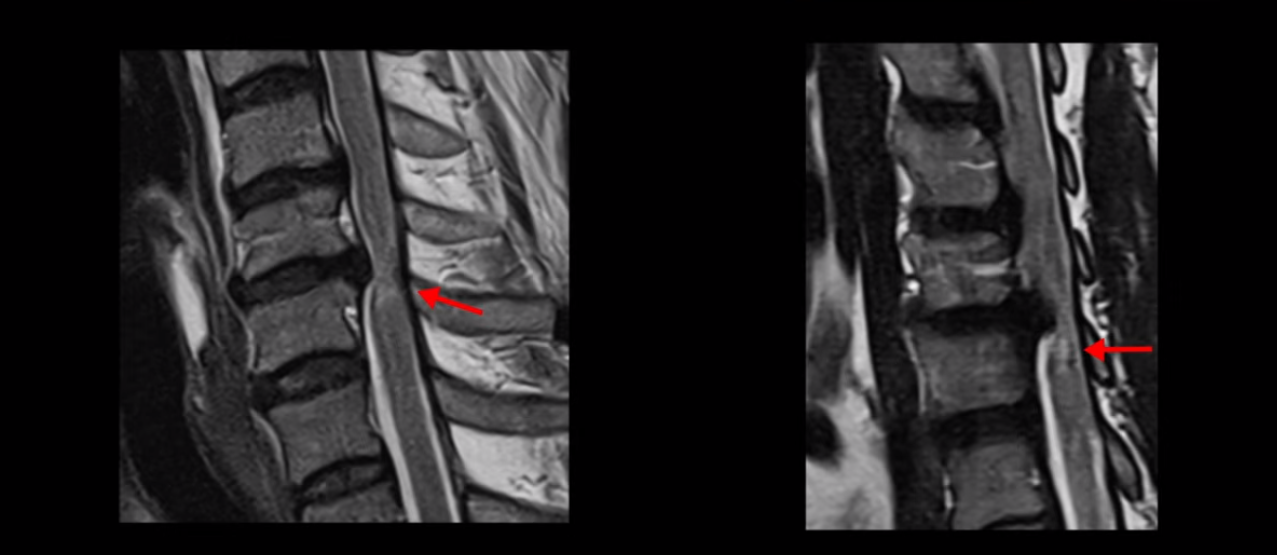

척수 신경이 눌리고 손상되니까 양쪽 손과 양쪽 다리 모두에 증상이 생깁니다. 양손에 힘이 빠지고 젓가락질이 힘들고, 단추 끼우기도 어려워지고 다리에 힘이 빠지니까 걷기도 힘들어집니다. 양손과 다리의 감각도 떨어지고요. 그래서 이 환자분은 수술하더라도 목 수술을 해야 하는데, 엉뚱하게도 허리 수술을 받습니다. 처음에 병원에 갈 때 허리도 원래 많이 아팠다고 하니까 그 병원에서 목 검사와 허리를 함께 검사해 보고 허리 협착도 심하니까 허리 수술을 먼저 하자고 합니다. 그래서 허리 세 마디를 수술했습니다.

MRI 보면 무려 3마디의 허리 뒤쪽, 후궁 뼈 한쪽을 거의 다 뜯어내고

황색 인대를 대부분 다 걷어냈습니다.

문제는 이 허리 협착이 양손과 양쪽 다리 힘 빠짐의 원인이 아니었기에 수술 후에도 증상이 전혀 좋아지질 않습니다. 그나마 다행인 건 허리 여러 마디를 수술하면서도 나사를 안 박은 겁니다. 수술로 인해 허리 여러 마디에 손상이 생기니까 걷기가 더 어려워져서 결국 저희 병원에 오실 때는 휠체어를 타고 오셨습니다.